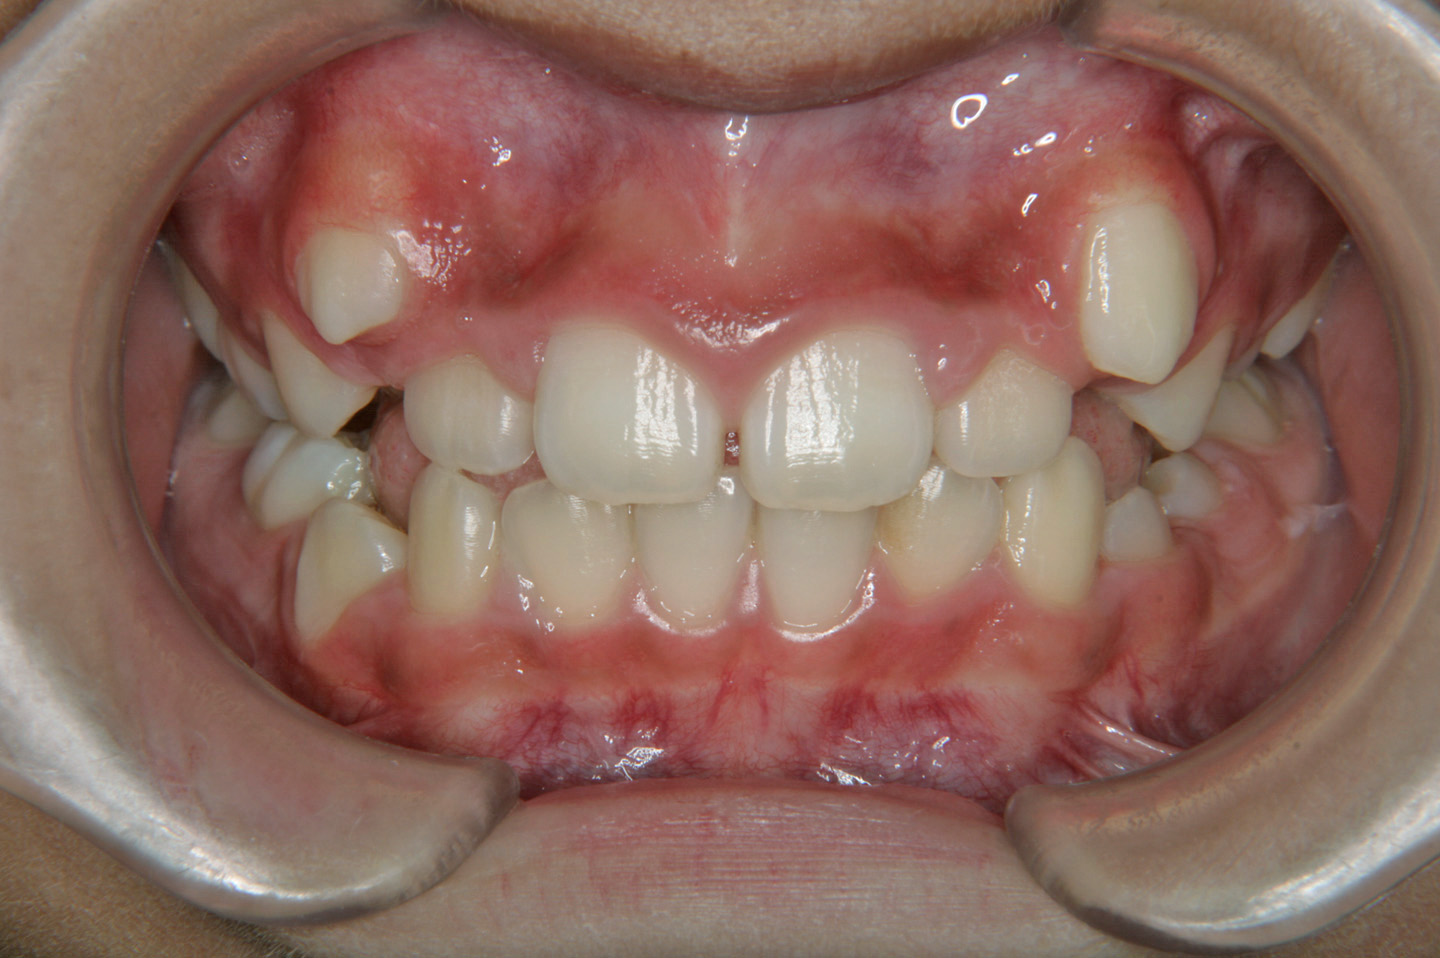

叢生(乱ぐい歯)

上顎前突(出っ歯)

八重歯を気にされて来院された10歳の女子です。上顎の叢生の程度は中程度で上顎第二大臼歯の萌出前であったので、ヘッドギアーとセクショナルアーチを用い、大臼歯の後方への拡大を行いました。その後、その空隙を利用して、非抜歯でエッジワイズ装置を用いて配列を行いました。拡大治療に2年、後期3年で治療いたしております。